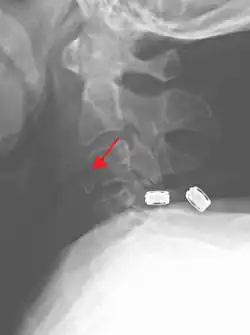

Radiographic detection

On CT scan or X-ray, a cervical fracture may be directly visualized. In addition, indirect signs of injury by the vertebral column are incongruities of the vertebral lines,[7] and/or increased thickness of the prevertebral space:[8]

X-ray of normal congruous vertebral lines